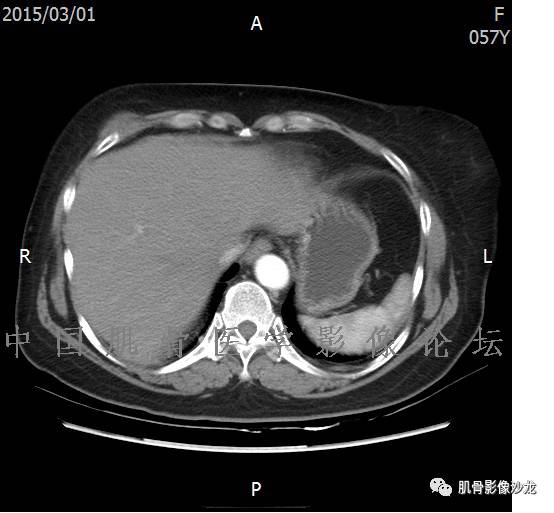

患者于2月前无明显诱因下出现腰骶部疼痛,夜间为重,逐渐加重伴左下肢麻木、疼痛,并有行走活动受限,在我院就诊,摄腰椎及骶髂部CT提示:腰椎骨质退变,腰3-4、4-5椎间盘膨出,骶髂关节炎。自用非甾体抗炎药无好转,再次来院就诊,门诊拟“骶髂关节炎”收住我科。病程无间歇性跛行,大小便正常。

专科检查:神清,脊柱无侧弯后凸畸形,椎体各节段无压、叩痛,双侧棘突旁无压痛,双侧骶髂关节压痛明显,左下肢放射痛,浅感觉较健侧减退,腰椎前屈后伸活动受限,膝、跟腱反射正常。

辅助检查:腰椎及骶髂部CT提示:腰椎骨质退变,腰3-4、4-5椎间盘膨出,骶髂关节炎。

雪舞 :第二例,位于骶骨,有骨质破坏并有软组织肿块,软组织肿块边界清

雪舞 :第二例挺难的,骨质破坏是溶骨性的,局部皮质中断,软组织肿块外缘光滑